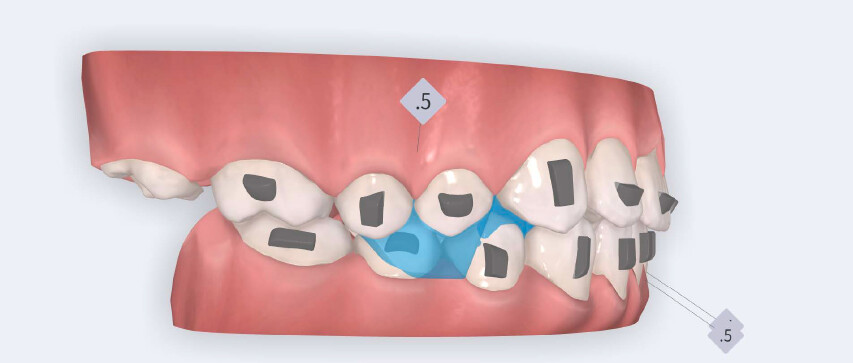

The treatment followed the Angel Aligner A6 mandibular advancement protocol, with the primary objective of achieving early correction of the sagittal discrepancy while simultaneously addressing dental alignment and transverse coordination.

The plan included:

- Initiation of mandibular advancement from the 4th aligner using mandibular advancement blocks;

- Arch expansion to resolve crowding and improve transverse coordination;

- Selective interproximal reduction in the mandibular anterior region to create space and control incisor inclination;

- Programmed intrusion of the maxillary central incisors to reduce the gingival display and correct the gummy smile;

- Intrusion of mandibular incisors and canines to level the Curve of Spee;

- Use of Class II elastics on Angel Buttons during the refinement phase to reinforce sagittal mechanics, introduced during the additional aligners stage.

The treatment was carried out using Angel Aligner clear aligners, with strict adherence to periodontal biological limits. Both maxillary incisor intrusion and transverse expansion were carefully monitored throughout the process to prevent any periodontal compromise. Mandibular advancement was initiated directly from the 4th aligner using advancement blocks, eliminating the need for a preliminary pre-advancement phase. The patient was at the CS3 stage of cervical vertebral maturation, corresponding to the pubertal growth spurt, a biologically favorable period for condylar remodeling and skeletal adaptation. A total of 35 aligners with advancement blocks were used, followed by 10 additional aligners incorporating Class II elastics on Angel Buttons to finalize rotations and alignment. With weekly aligner changes, the overall treatment duration was approximately 45 weeks (10 months), aligning with the expected biological timeline for condylar remodeling. For mandibular anterior intrusion, the Frog Protocol combined with interproximal reduction (IPR) achieved complete leveling of the Curve of Spee.